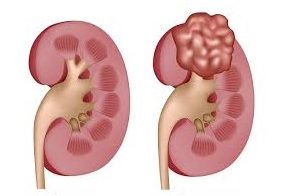

Kidney cancer is a malignant cell growth in the kidney (a tumor). The medical name is renal cell carcinoma. Tumors can also be benign.

Kidney cancer is a general term. There are different tumor types and different disease stages in the kidney. Your treatment and experience, will depend on the characteristics of the tumor and the experience of your medical team.